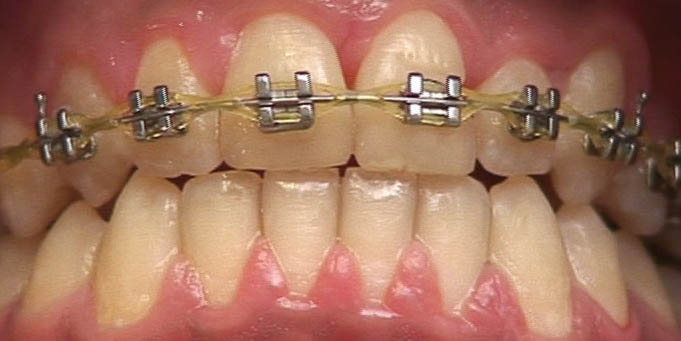

اگر در ابتدای درمان دیواره دیستالی به سمت لبیال چرخش داشته باشد باید روتیشنوج را بر روی بالچههای دیستالی بگذارید. اگر دیواره مزیالی به سمت لبیال چرخش داشته باید روتیشنوج را بر روی بالچههای مزیالی بگذارید، در این بیمار روی بالچههای دیستالی میگذاریم (شکل 171-1). بعد سیم 0.019x0.025 حرارتی را قرار دهید. شما نمیتوانید oring روی این براکت بیندازید، لذا وایر لیگاچور کنید. این روتیشنوج بایستی تا انتهای درمان بماند و همیشه روی براکت آن وایر لیگاچور شود (شکل 172-1). فقط در 4-2 هفته آخر که مرحله استقرار (فاز Settling) است باید آن را در بیاوریم تا قبل از خارج کردن براکتها، تمام دندانها مرتب باشند.

شکل 171-1: بعد از مرتب شدن انسیزور در شکل 166-1، روتیشن وج روی نیمه دیستالی میگذاریم، بعد آرچ وایر 0.019x0.025 حرارتی را روی آن قرار میدهیم تا باعث لینگوالی شدن بیشتر دیستال آن بشود.

شکل 172-1: وقتی 0.019x0.025 استیل را میگذارید باید روتیشن وج بماند.